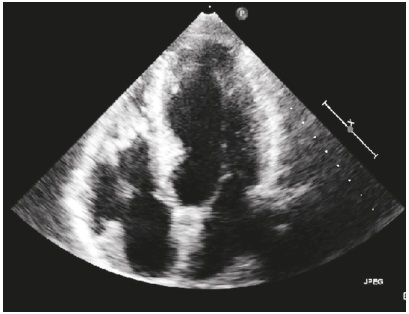

La ecocardiografía transtorácica mostró hipertrofia ventricular izquierda severa, grosor de la pared posterior en sístole de 17 mm, sin dilatación ventricular ni trastornos segmentarios de la contractilidad, con flujo valvular por doppler de color normal, válvulas sin alteración morfológica y función ventricular sistólica izquierda conservada, con fracción de eyección del 75 % calculada por el método de Simpson (Figura 2).